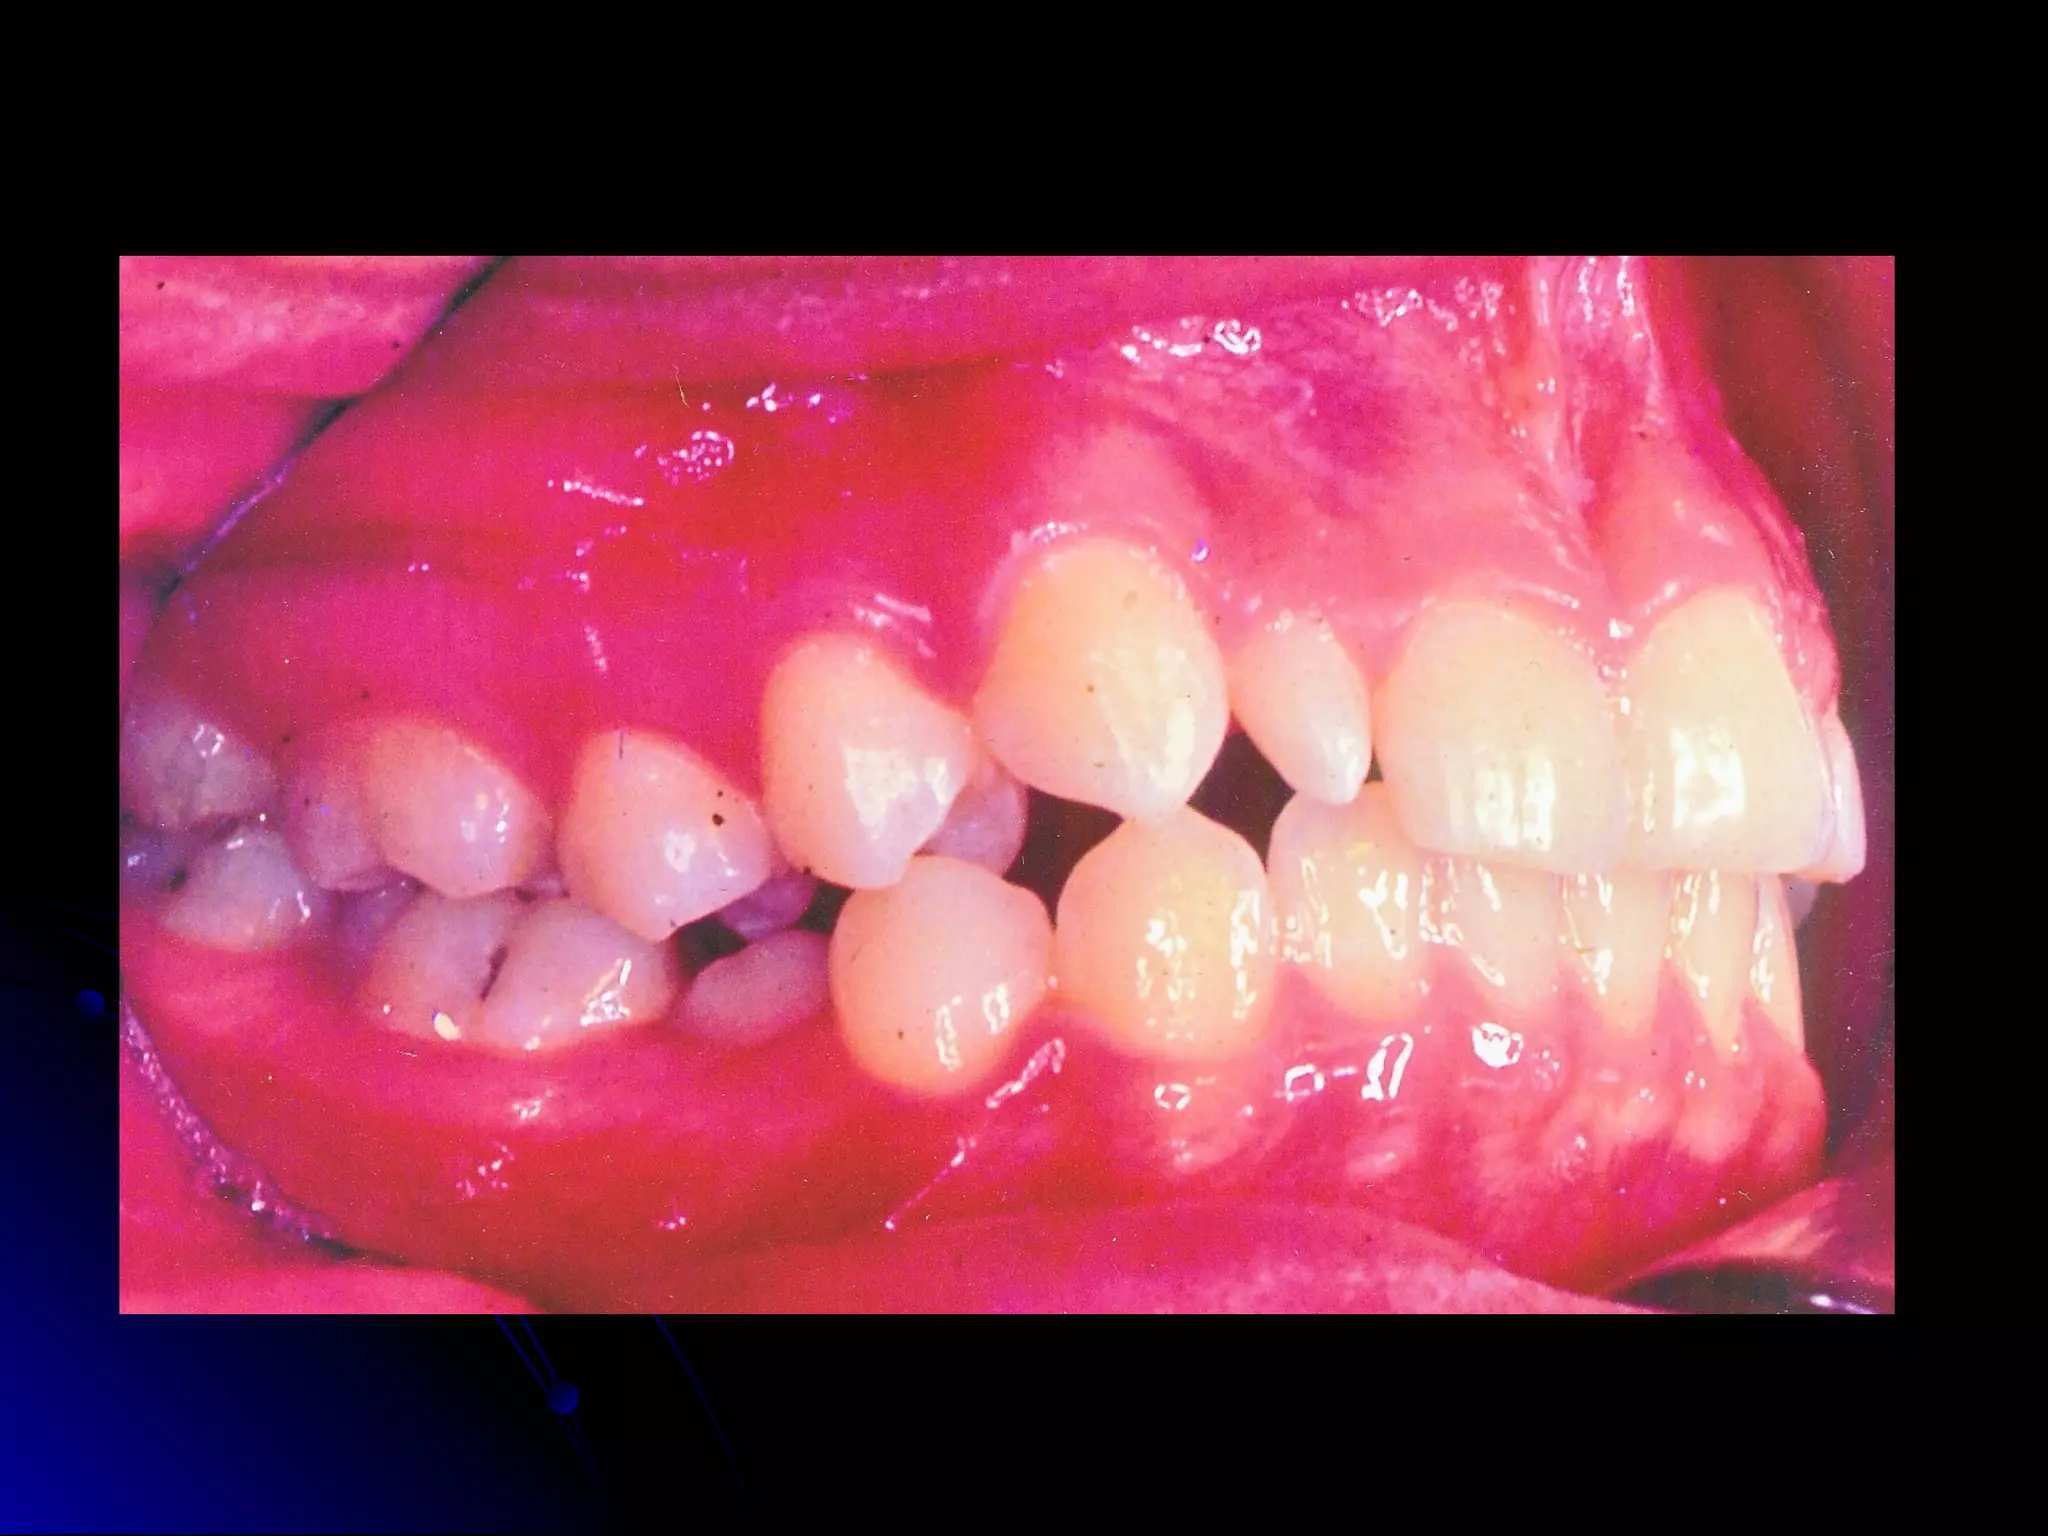

CLASS I MALOCCLUSION.

There may be crowding, spacings, rotated teeth,

supernumerary tooth etc.

Supernumerary teeth

Fused teeth

ANGLE’S CLASSIFICATION OFMALOCCLUSION. CLASS I MALOCCLUSION. Mesiobuccal cusp of upper first permanent molar occludes into the buccal developmental groove of the lower first permanent molar. Line of occlusion is incorrect. There may be crowding, spacings, rotated teeth, supernumerary tooth etc.